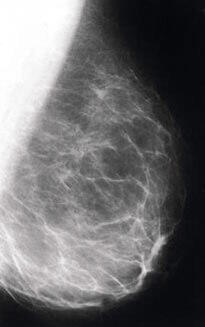

- Cancer du sein

Les études épidémiologiques, des études animales et des essais cliniques semblent indiquer que le soja et les isoflavones de soja protègent du cancer du sein. Des études épidémiologiques démontrent une relation inverse entre la consommation de soja et l'incidence de cancer du sein. Les Américaines ont un taux de cancer du sein deux à trois fois plus élevé que des Asiatiques suivant leur alimentation traditionnelle.

Une étude contrôlée, publiée en 1997 dans The Lancet, a examiné les effets des phytoœstrogènes sur le risque de cancer du sein. Cent quatre femmes avec un cancer du sein débutant diagnostiqué ont été comparées à un nombre équivalent de témoins. Avant le traitement, un questionnaire ainsi que des tests urinaires et sanguins ont été réalisés. Une augmentation de l'excrétion urinaire d'isoflavones était associée à une réduction du risque de développer un cancer du sein16.